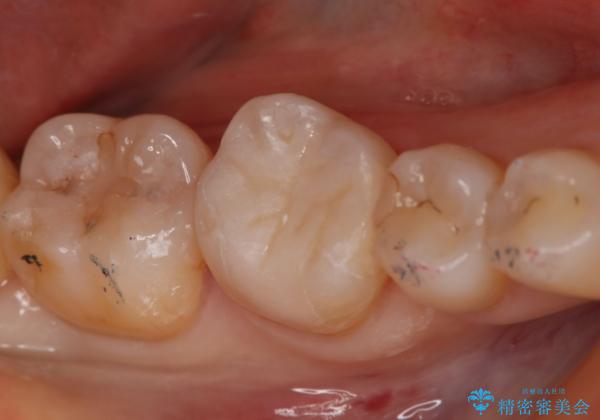

- 右下6番のメタルインレー脱離のため来院。

セラミックの治療を希望されたため切削量を考慮し、セラミックインレーでの治療を選択しました。

う蝕が深くまで進行していたので、CRで裏層した上で形成・印象をしています。